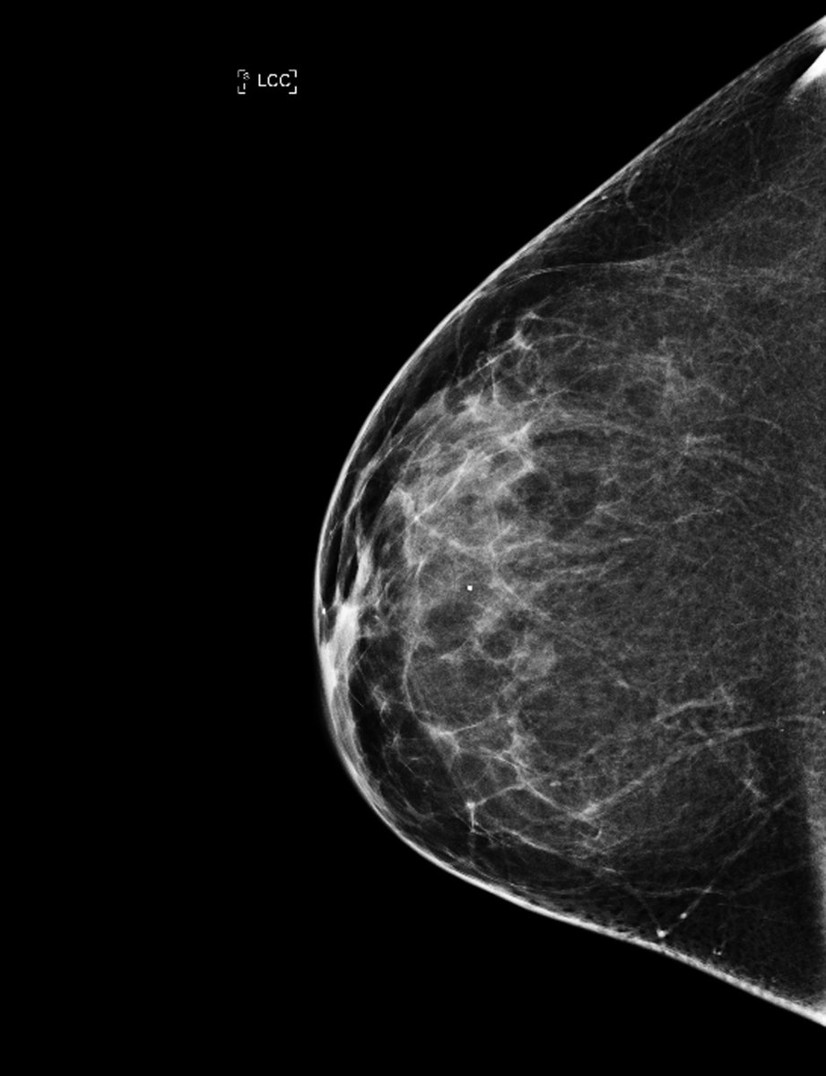

Screeningprogrammet for brystkreft har reddet Vigdis og Line Norman Hjorth. Det har også resultert i en viktig bok. Men er screening bare av det gode?